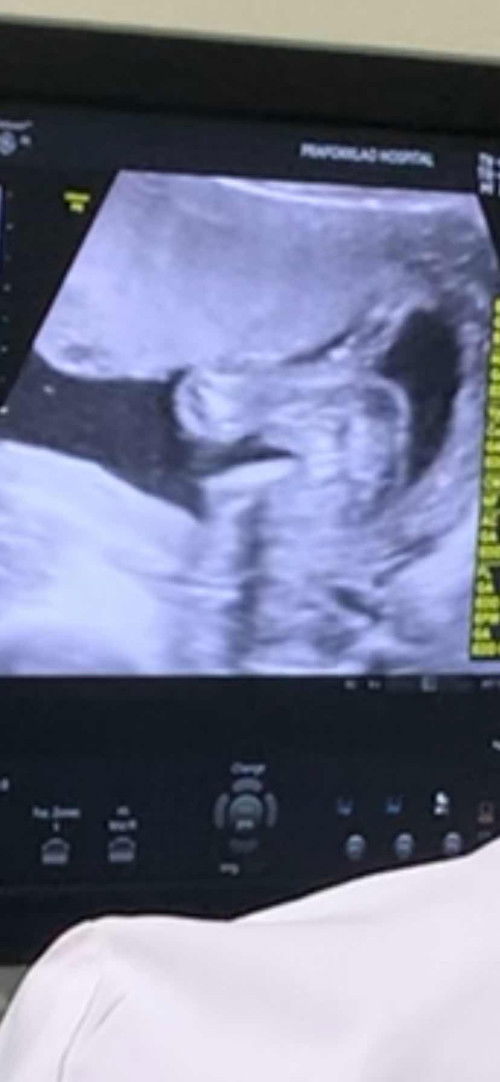

แบบนี้แม่ๆคิดว่าผู้หญิงหรือผู้ชายคะ

หมอบอกแค่ว่ามันเรียบๆอาจจะผู้หญิง ทางนี้ดีใจรอแล้วค่ะ